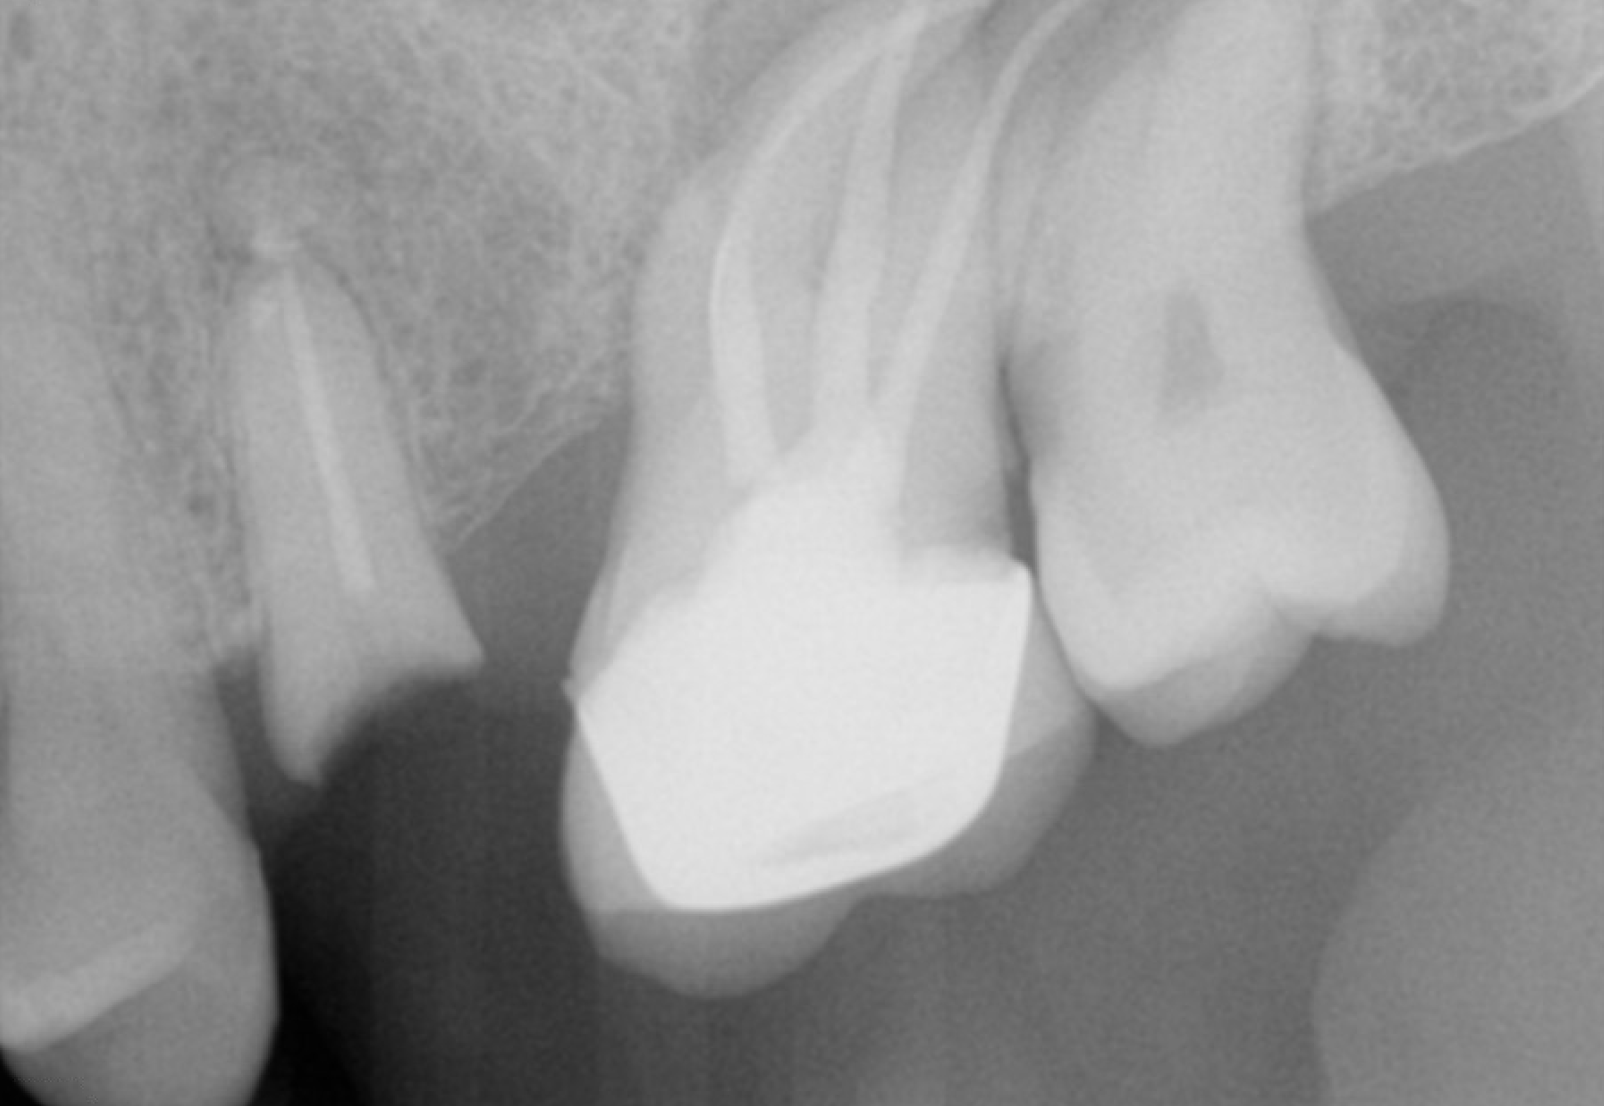

- 骨の減り方

- 歯の揺れの強さ

- 噛み合わせの崩れ方

- 清掃しやすい形に戻せるか

ここを見ないまま治療を急ぐと、途中で計画が変わりやすくなります。